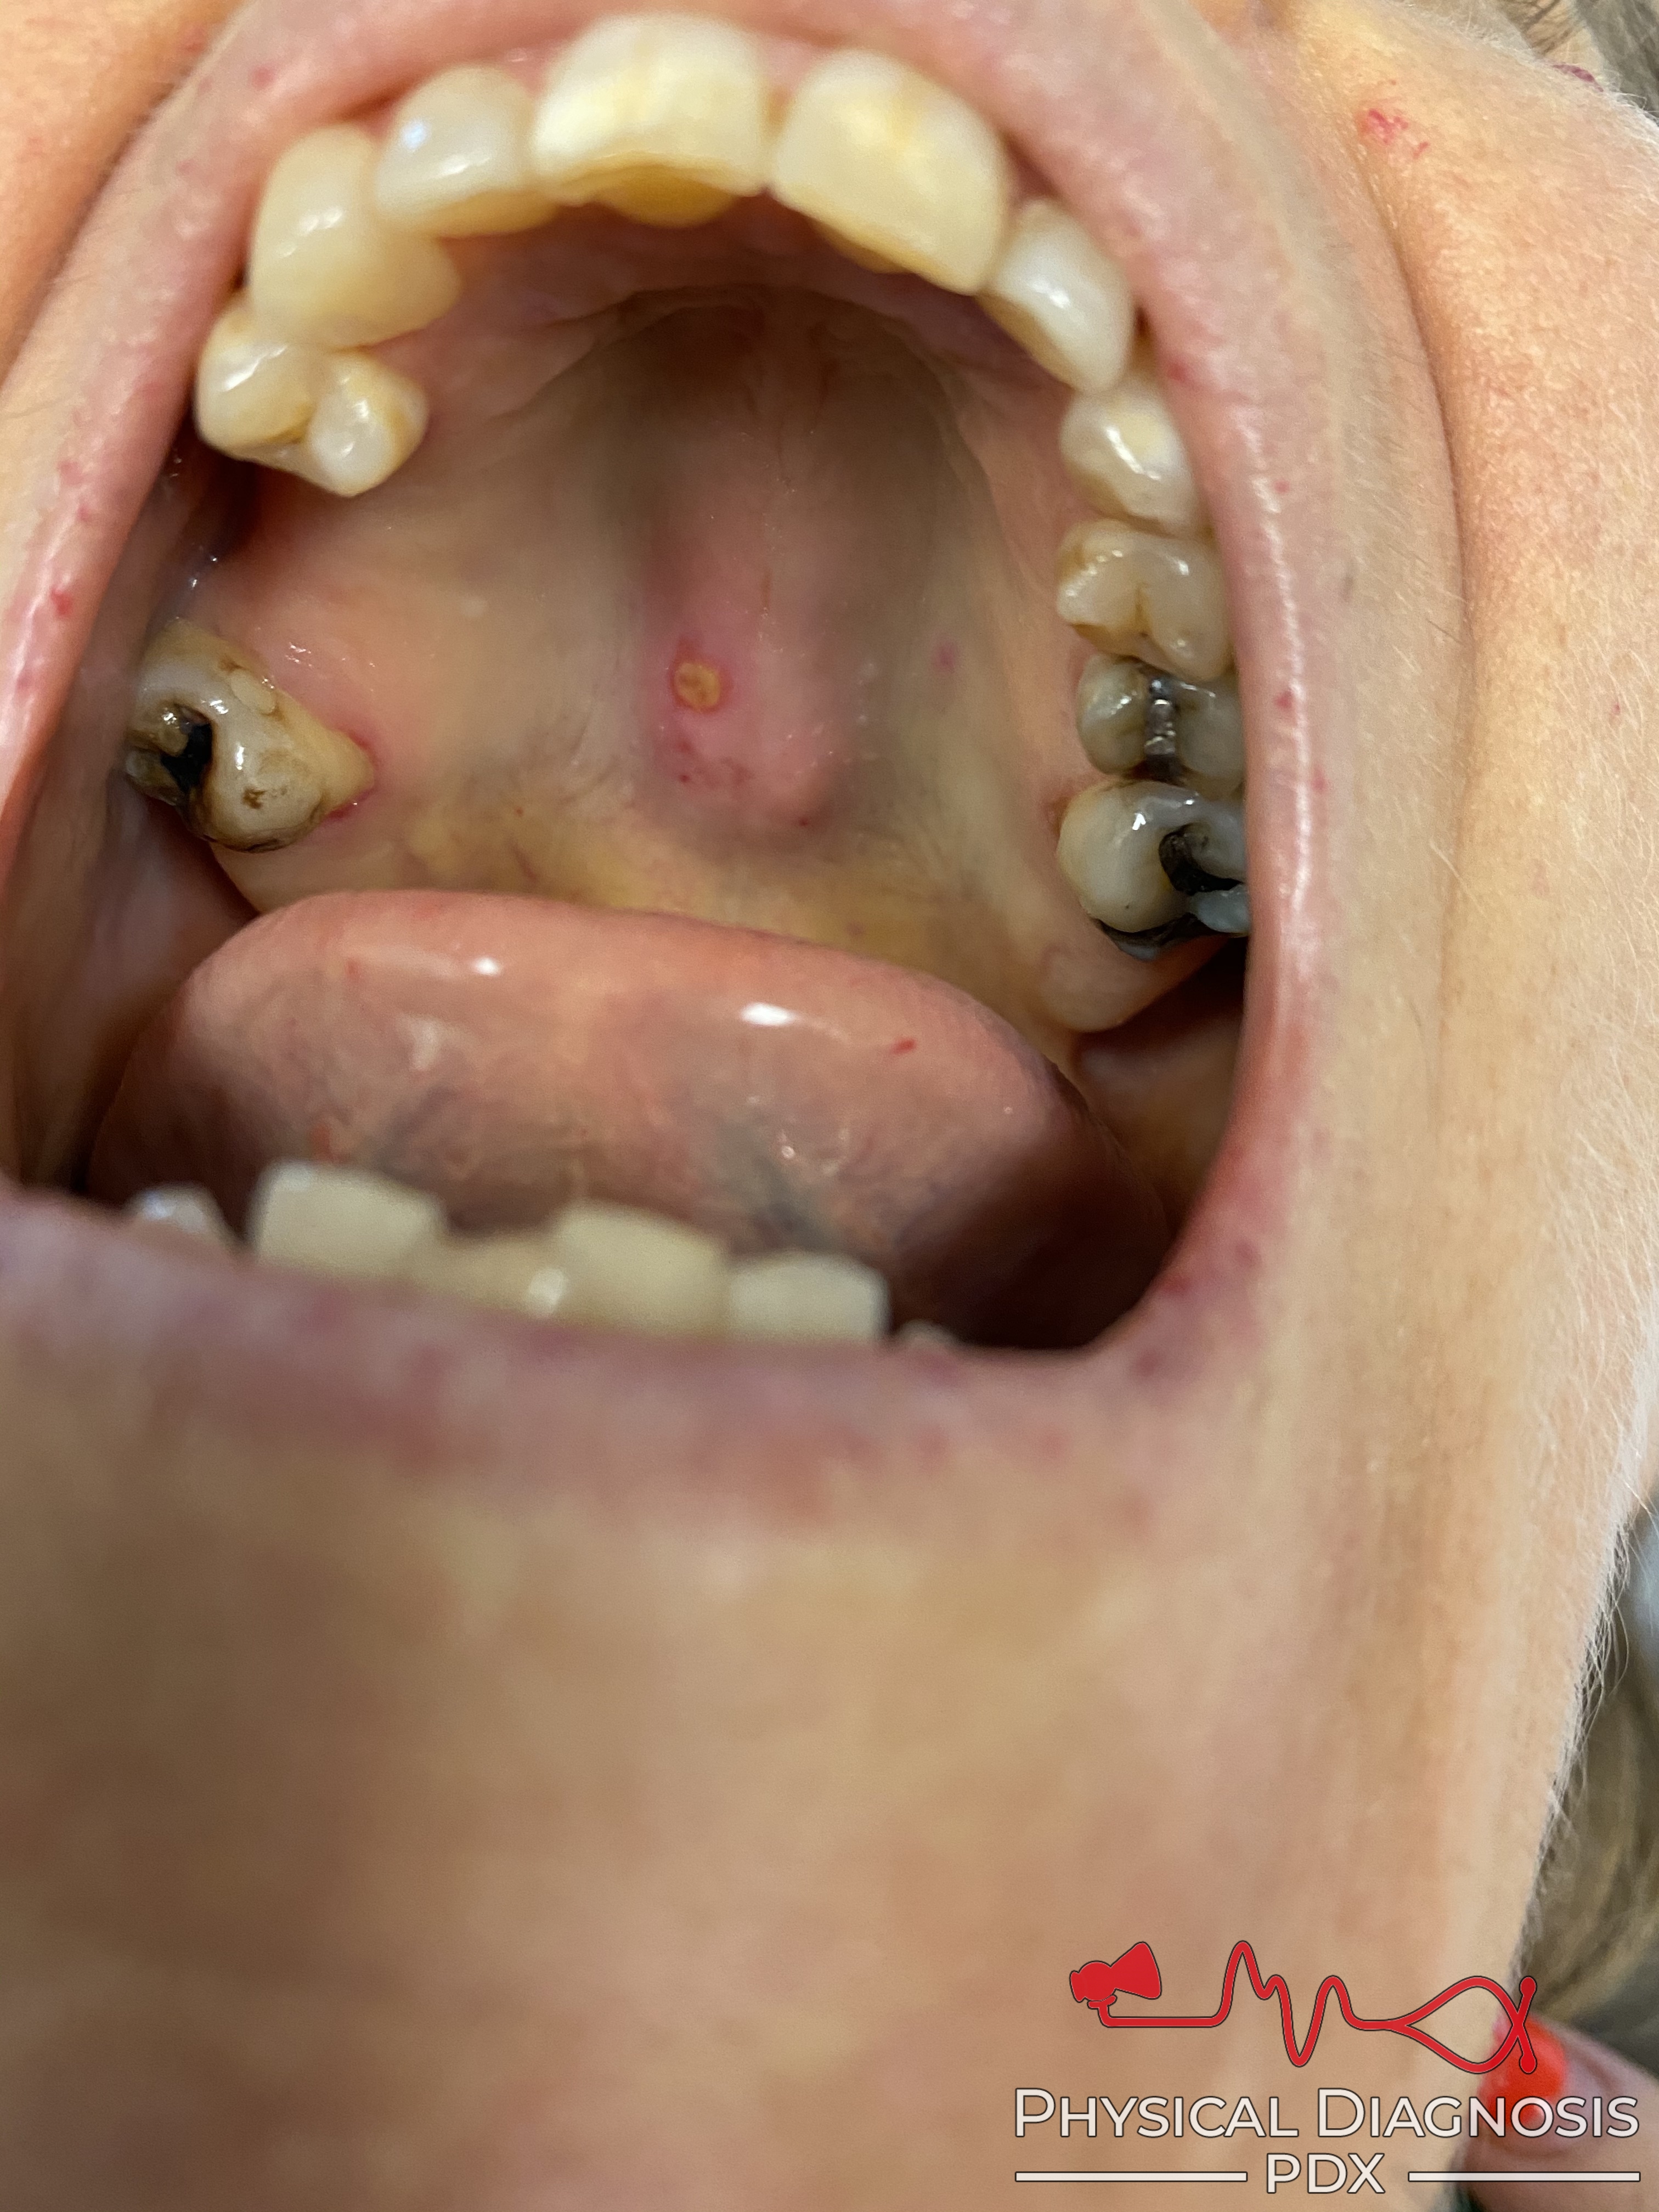

Hereditary Hemorrhagic Telangiectasia

This is a middle-aged woman with hereditary hemorrhagic telangiectasia who was admitted to the hospital for an unrelated reason.